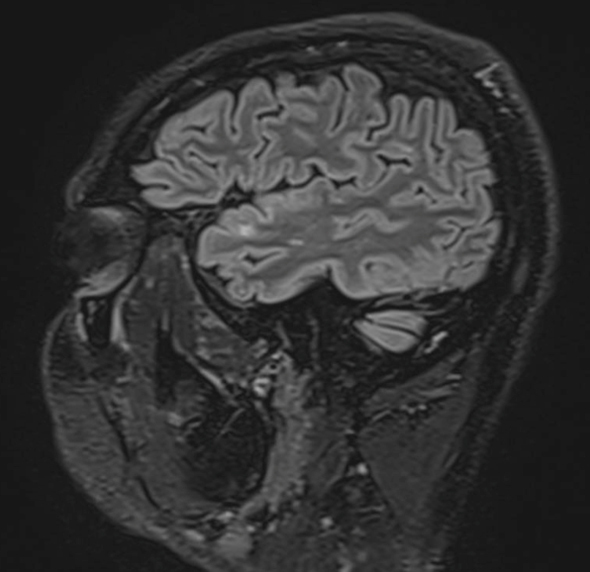

M. C., 45 ans, consulte au mois d’avril en cabinet de neurologie. Il a une sensation de vertiges et de vision double.

Le patient rapporte depuis trois semaines une diplopie lorsque ses deux yeux sont ouverts, qui disparaît à l’occlusion d’un œil. Il rapporte aussi une sensation d’instabilité à la marche avec une faiblesse de l’hémicorps gauche qui s’aggrave progressivement. Il ne décrit pas de sensation de rotation de lui-même ou de la pièce. Il a vu un ORL qui a prescrit un traitement symptomatique des vertiges, sans efficacité, raison pour laquelle il vous consulte.

– sensibilité : hypopallesthésie distale des membres inférieurs, ataxie proprioceptive aux quatre membres mais prédominant à l’hémicorps gauche, nettement aggravée à la fermeture des yeux. Pas d’hypoesthésie à la piqûre ;

– diplopie binoculaire sans paralysie oculomotrice. Pas d’autre anomalie à l’examen des paires crâniennes.